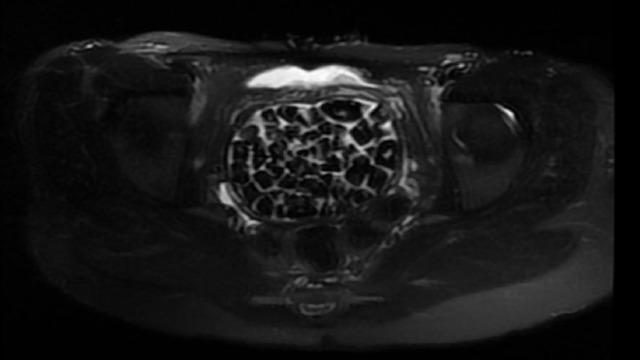

Hastasının durumuna yönelik konuşan Üroloji Uzmanı Doç. Dr. Erkan Erkan, "Hastamızın 2004 yılında doğduğunu ardından doğar doğmaz ekstrofi vezika dediğimiz 50 binde bir görülen bir anomaliden dolayı art arda ameliyatlar geçirdiğini öğrendik. 10 yaşında yine bir ameliyat geçirmişti, gerekli görüntüleme ve tetkiklerimizi yaptırdık. Normalde mesanesinin olması gereken yerin hemen arka kısmında taşlarla dolu bir kese olduğunu gördük, bunun üzerine ek görüntülemeler; MR çektirdik. Hastamız çelişkili açıklamalar almıştı, kendi radyolojik kliniğimiz ve edindiğimiz konsültasyonlarda taşların mesanede değil vajinal boşlukta oluştuğunu düşündük, bir planlama yaptık. Kadın doğum hocamızın da çabasıyla taşları tamamen temizledik ardından ileride normal bir hayat sürmesi bakımından oraya plastik cerrahi yaptık. 287 adet taş çıkardık, pratikte gerçekten görünce çok şaşırdık çünkü bu aynı zamanda literatürde çok nadir görülen bir olay. Biz ameliyata hazırlanırken de teorik olarak biraz araştırdık. Literatürde gördüğümüz kadarıyla buna benzer bu tanıma uyan bir vaka vardı. Literatürde sanırım yayınlanmış 2’nci vaka olacak. Farkındalık çok önemli, bilinçli bir hastamız vardı. Doğumsal anomaliyle doğan çocuklarımızda ileride bunlara bağlı bazı sıkıntılar çıkabileceğinin öngörülmesi lazım. İlgili tedavilerini alsalar bile düzenli takiplere gelmeleri gerekiyor. İleride eğer dikkat etmezse ki zannetmiyorum, tekrarlayabilir. Bu rahatsızlık ekstrofi vezikal epispadias durumu çok nadir bir durum" dedi.

Genç kızın uzun süredir devam eden karın ağrısı olduğunu söyleyerek sözlerine başlayan Jinekolojik Onkoloji Uzmanı Op. Dr. Emin Erhan Dönmez, "Mesane taşları olduğu düşünülerek daha büyük bir hastaneye refere edilmiş. Aramızda mini bir konsey yaparak muayene ettik. Vajen bir hazne görevi görerek orada durağan bir idrar, uzun süre beklediği için idrar içindeki minerallerde çökerek taşlar oluşmuş. Mesanedeki idrarın vajene akmış olabileceği ve vajende göllenen idrar nedeniyle taşların burada oluşacağını düşündük, ameliyatımızı planladık. Ameliyata tanı amaçlı girmiştik, sistoskopi (Mesane gibi idrar yollarını kapsayan kısımlardaki rahatsızlıkların teşhis ve tedavisinde kullanılan endoskopik bir yöntem) dediğimiz ameliyatı Erkan Hocam ile birlikte gerçekleştirdik. Önce mesaneyi bir görüntüledik, mesane tabanına yaklaşık 2-3 cm’lik bir alandan vajene fistülize olduğunu gördük. Mesaneden vajene geçtiğimiz esnada tüm vajenin taşlarla dolu olduğunu gördük. Tanı amacıyla girdiğimiz ameliyatta her şey de olağan gittiği için tedaviye geçtik. Taşların çıkabileceği kadar bir genişlik sağladık. Daha sonra yaklaşık en büyüğü 2,5 cm boyutlarında olan, irili ufaklı 287 tane taşı ameliyat esnasında çıkarmış olduk. Taşların tekrarlamaması için idrarın göllenmemesi, en azından dışarıya rahatça boşalabilmesi için vajinal rekonstrüksiyonu sağladık. Ameliyatta da herhangi bir problem yaşamadık. Literatürü Erkan Hocam ile birlikte değerlendirmiştik. Primer olarak vajende birikmiş olan bu kadar çok sayıda taşla ilgili bir makale görmedik, rastlamadık" dedi.